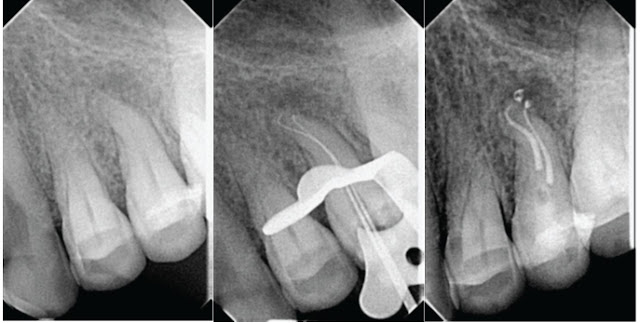

Một bệnh nhân nữ 32 tuổi tới phòng khám của một trong các tác giả (Ricardo Machado) với cơn đau khủng khiếp khi có kích thích lạnh ở cung hàm trên bàn trái. Tiền sử bệnh nhân không có gì đặc biệt. Tất cả các răng trong vùng đều đáp ứng trong khoảng bình thường với các thử nghiệm nhiệt và điện trừ răng hàm nhỏ thứ nhất hàm trên cho thấy một đáp ứng quá mức. Dùng sonde nha chu cho thấy các răng có túi lợi 3mm. Phim chụp trước xử trí cho thấy có lỗ sâu chung quanh chụp răng và ống tủy dạng S (Hình 3a). Sau khi tổng hợp các dữ liệu, tác giả chẩn đoán đây là một viêm tủy không hồi phục.

Sau khi gây tê thấm (Articaine 1:100000 epinephrine), tác giả đặt đê. Đường vào được mở bằng mũi 1016 HL và hoàn thiện bằng mũi Endo Z. Loại bỏ các cản trở bằng trâm máy Protaper SX, S1 và S2 10.

Tiếp cận vùng S bằng trâm K số 10. Chiều dài làm việc được xác định bằng máy định vị chóp Elements Diagnostic Apex Locator. Thăm dò bằng cách đưa chậm các trâm K tới chiều dài làm việc và thao tác đè nhẹ vào thành ống tủy. Việc này sẽ giúp tạo ra một đường vào dụng cụ trơn tru dọc theo độ cong chữ S với ít dụng cụ nhất trong quá trình tạo hình.

Sau đó, dùng kỹ thuật bước xuống với các profile từ số 04 tới 30. Bơm rửa bằng NaOCl 2.5% sau mỗi dụng cụ được sử dụng. Để trách tắc ống tủy, giữa các mũi file máy sử dụng, ta cân dùng trâm K 10 để thông ống tủy. Sau đó ống tủy được bơm rửa bằng EDTA 17% trong 3 phút và thấm khô bằng côn giấy 30 , trám bít bằng Kỹ thuật lai Tagger.

Hai côn gutta chính (Profile.04- Dentsply Maillerfer, Ballaigues, Switzerland) được đặt vào ống tủy rồi chụp phim kiểm soát. Các cây côn được phủ AH Plus Sealer (Dentsply DeTrey, Konstanz, Germany) và đặt tới chiều dài làm việc với sự giúp đỡ của cây lèn số 30 (Dentsply Maillerfer, Ballaigues, Switzerland). Tiếp đó, đặt 3 côn phụ. Dùng lây lèn McSpadden 40/0.2 ở 2/3 ống tủy. Răng được trám tạm bằng Cavit (ESPE, Seefeld Oberb, Germany) và bệnh nhân được đặt hẹn quay lại để hàn vĩnh viễn